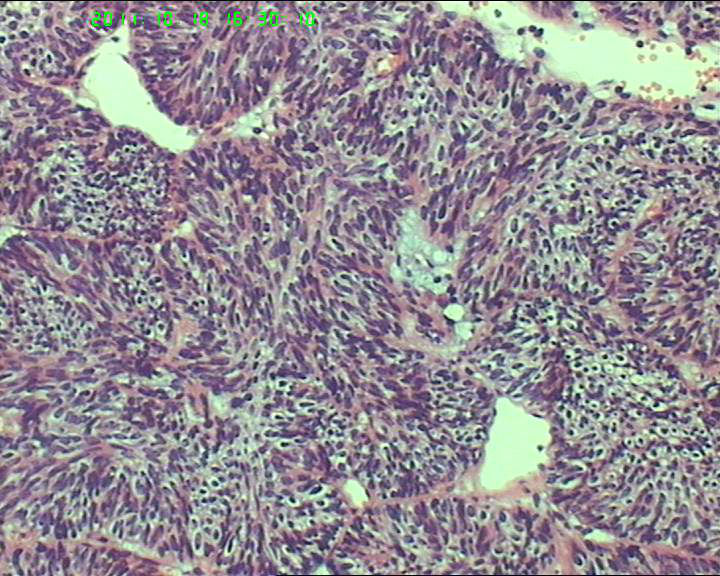

70岁女性体检发现膀胱肿物,是癌吗?

膀胱后壁一2*1cm大小肿物